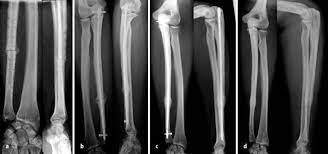

Bei den dabei verwendeten sogenannten Marknägeln handelt es sich meist um Implantate aus Titan oder Edelstahl. Die Diagnose Multiples Myelom in Deutschland fälschlicherweise oft mit dem solitären Plasmozytom gleichgesetzt löst Schock Angst und Ratlosigkeit aus. Es blieben subtrochantär große Löcher im Femur mit einer lateralen kortikalen Lücke von 12x12 mm und einer weiteren.

Immerhin wird das Bein bin zum Knochen geöffnet Gewebe und Muskeln durchtrennt und es verbleiben Löcher in den Knochen. Die Schraube im Schenkelhals ließ sich noch lösen die zwei Verriegelungsschrauben jedoch nicht - die Schraubenköpfe brachen ab die Gewinde wurden überbohrt und brachen wieder ab. Da die Drähte bei auch nur leichter Lockerung eine Gefahr für Strecksehen darstellen gibt es sehr gute Gründe die Kirschnerdrähte zu entfernen.

In so einem Fall ist es sinnvoll nach der Metallentfernung Reha und. 1 2 3 4 5 6. Das liegt oft an der Fehlstellung die durch die erlittene Verletzung hervorgerufen wurde. In so einem Fall ist es sinnvoll nach der Metallentfernung Reha und. Auf dem einen Bild hängt ganz vorne am Schlüsselbein nahe hals eine Spitze aus dem Knochen die je nach Bewegung oder Berührung auch Weh tut Leider nicht so gut zu erkennen auf dem Bild. Komplizierte Brüche können nach der Metallentfernung immer noch Schmerzen bereiten. Immerhin wird das Bein bin zum Knochen geöffnet Gewebe und Muskeln durchtrennt und es verbleiben Löcher in den Knochen.